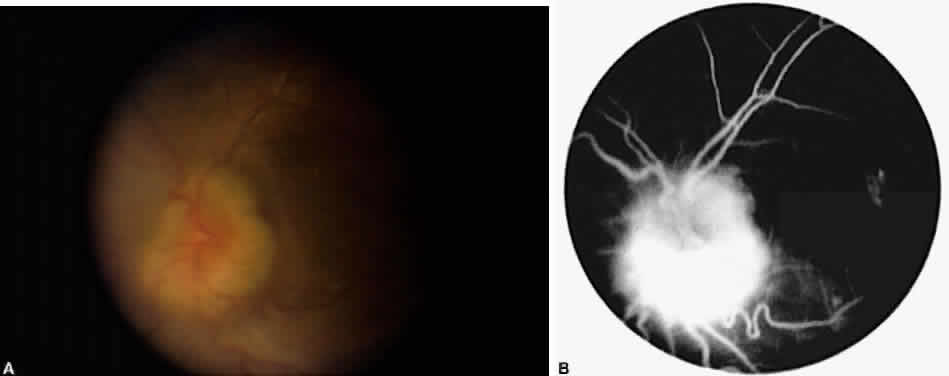

Cystoid macular edema (CME) is by far the most common macular sequela of

chronic inflammation, although retinal and subretinal neovascularization, preretinal

membranes, macular ischemia, and macular holes can also

occur.41–43 Chronic CME and its sequelae are a significant cause of visual morbidity

and probably account for the majority of cases of low visual acuity (20/40) in

uveitis patients (Fig. 5).44–46 The main symptoms experienced by patients with CME are decreased vision

and metamorphopsia, often with marked fluctuations in acuity. The diagnosis

of CME is often difficult and may require careful stereoscopic

examination at the slit lamp with a contact, Hruby, 78 or 90 D lens. Frank

cystoid changes may not be present, and often only a loss of the

normal foveal reflex is seen. For cases in which the diagnosis is not

clear, fluorescein angiography is a helpful tool. This demonstrates leakage

from perifoveal capillaries, with or without the characteristic

petaloid hyperfluorescence in the late phases of the angiogram.